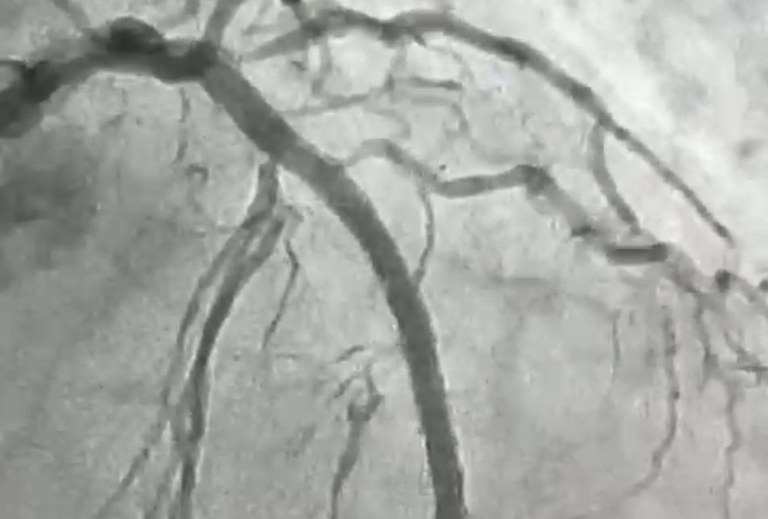

O procedimento foi realizado em uma paciente de 84 anos, moradora de Itaporanga, que apresentava uma lesão grave e altamente calcificada na artéria descendente anterior, considerada a principal artéria do coração. Segundo o cardiologista intervencionista, Jeann Santiago, um dos médicos responsáveis pela realização do procedimento, a condição exigia um tratamento extremamente delicado, com risco elevado, devido à dureza da placa obstrutiva, comparada pelos médicos a uma “pedra” no interior do vaso.

Para possibilitar a abertura da artéria, a equipe utilizou a aterectomia rotacional, técnica que funciona como uma microfuradeira capaz de desgastar e desobstruir placas de cálcio muito rígidas. Em seguida, com o auxílio do ultrassom intravascular, foi possível medir com precisão a extensão da lesão e determinar o tamanho ideal dos dispositivos a serem implantados. Após a preparação do vaso, foram colocados dois stents farmacológicos, completando o processo de revascularização”, explicou o cardiologista.